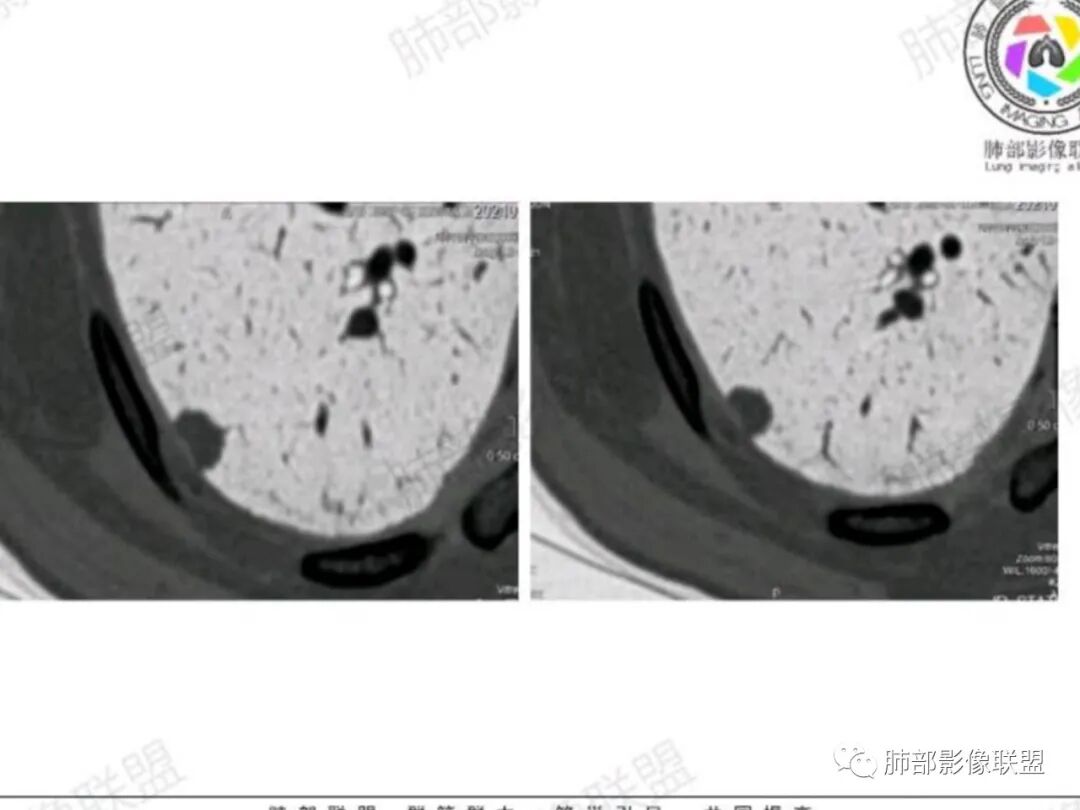

不过胸膜重建是“圆洞”不是“裂隙”,好像 更多见于良性

男,63,体检发现肺部结节。胸部CT:右肺下叶胸膜下类圆形实性结节影,边界清楚,边缘膨隆、短毛刺,细支气管在病灶边缘截断,小血管进入,胸膜牵拉圆洞样凹陷,胸膜外脂肪间隙增宽。增强密度不均匀,内有点状低密度。引流区域淋巴结增大?考虑恶性,腺?小?鉴别PC、TB等肉芽肿。

右肺下叶胸膜下结节,膨隆为主,细小毛刺,增强静脉期较动脉期变化不大,密度不均匀,体检发现,邻近胸膜有牵拉,重建呈圆洞样改变,良恶性征象都有,老年人,孤立结节,按恶性对待,腺癌或转移瘤>炎性肉芽肿,建议穿刺活检

腺癌>炎性肉芽肿,胸膜表面重建示洞周洞底光整,多见于良性结节,粘液腺癌也可。

腺癌,不鉴别(靠肺内侧明显膨隆,毛刺,胸膜侧凹陷,两端与胸膜接触处有微积液,胸膜接触面无增厚,增强中度强化),收缩力相对偏弱,病理类型可能是腺泡为主,也可能是结节型粘液腺癌。

首先,靠肺内侧明显膨隆,毛刺,胸膜侧凹陷,局部胸膜有黏连(不是增厚,是侵润),两端与胸膜接触处有微积液,增强中度强化,就可以基本确定恶性,然后收缩力相对偏弱,胸膜重建洞较圆,病理类型就可能是结节型粘液腺癌。

我思考了一下,觉得结节性粘液腺癌的特点,恶性征象+收缩力偏弱+炎性征象